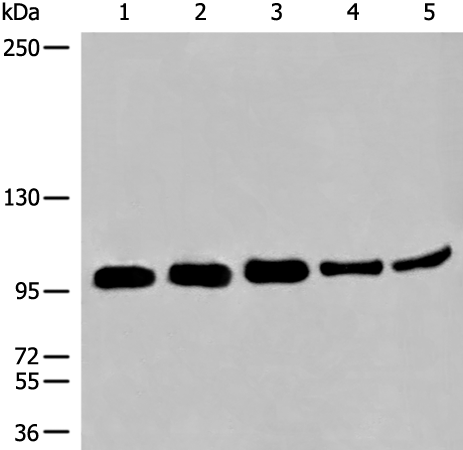

分类: 科研抗体货号: P13209别名: FCC1; COCA1; HNPCC; LCFS2; HNPCC1应用: WB,IHC反应种属: Human, Mouse